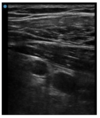

Not at all

infraclavicular